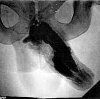

Кавернозография. Рентгенологическое исследование сосудов эрегированного полового члена с использованием контраста, введенного в кавернозное тело. Он позволяет получать информацию о состоянии венозной системы и кавернозных тел, выявлять сосуды, через которые осуществляется патологический отток крови, выявлять фиброзные бляшки, склероз или атрофию в кавернозном теле. Кавернозография является основным методом, используемым для дифференциальной диагностики артериогенной и веногенной эректильной дисфункции. Он используется для оценки важности различных патогенетических механизмов у пациентов с эректильной дисфункцией смешанного происхождения. Назначен на заключительном этапе обследования. Это может быть выполнено в амбулаторных или стационарных условиях. Не требует специальной подготовки.

Кавернозография - это классический метод ангиографии, используемый на последних этапах диагностики эректильной дисфункции. Содержит несколько изображений эрегированного полового члена, которые были записаны в динамике в разных проекциях. Кавернозография считается золотым стандартом в области дифференциальной диагностики и выявления причин эректильной дисфункции в сложных случаях. Точная оценка важности венозного компонента для развития эректильной дисфункции может значительно повысить эффективность лечения этой патологии. В дополнение к ультразвуковой визуализации полового члена и кавернозометрии, кавернозография включена в список обязательных диагностических процедур, необходимых для подозреваемой органической эректильной дисфункции. Это минимально инвазивный метод обследования. Гарантирует, что использование ионизирующего излучения назначается только при наличии достаточных доказательств.

Оценка результатов

Исследование позволяет определить причину эректильной дисфункции при потере вен и кавернозных тел полового члена. При обработке результатов кавернозографии, патологического венозного оттока, можно обнаружить наличие патологических шунтов между кавернозными телами и губчатым телом. Кроме того, каверноскопия позволяет выявить участки склероза и атрофии в кавернозных телах, вызванные предшествующими заболеваниями и травмами, фиброзными изменениями в оболочке кавернозных тел при болезни Пейрони и врожденными нарушениями структуры кавернозных тел или венозной сети полового члена. При травматических поражениях полового члена кавернозография указывает на наличие скопления контраста в зоне повреждения сосудов и кавернозных тел.

Отсутствие нарушений при кавероскопии указывает на артериальную природу органической эректильной дисфункции. Исключение психогенной эректильной дисфункции, как правило, не является необходимым, поскольку это выполняется на более ранней стадии дифференциальной диагностики. При эректильной дисфункции смешанного генеза кавернозные данные сравниваются с результатами других диагностических процедур (УЗИ полового члена, интракавернозный тест ), Что позволяет получить полную картину влияния нескольких патогенных механизмов на эректильную дисфункцию. терпеливые отношения.